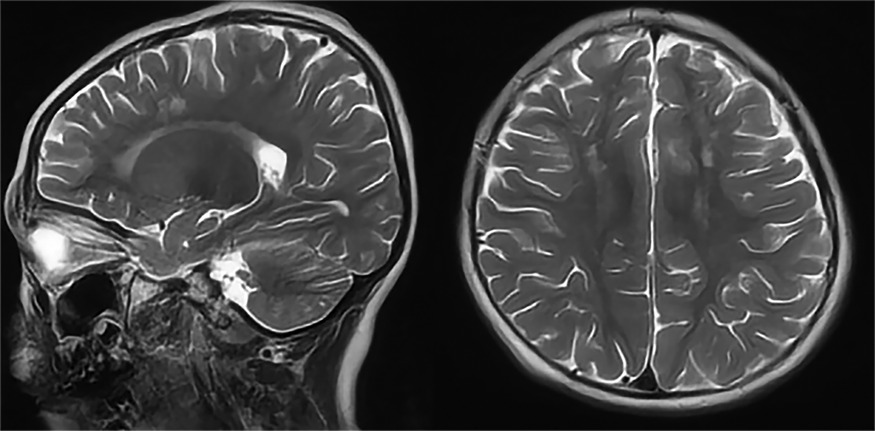

Диагностический комплекс анализирует метаболические процессы в тканях мозга, отслеживая утилизацию глюкозы с помощью фтордезоксиглюкозной позитронно-эмиссионной томографии. Система сопоставляет полученные изображения с обширным архивом медицинских данных и выявляет характерные метаболические сигнатуры различных патологических процессов.

StateViewer успешно дифференцирует патологические изменения, характерные для различных форм деменции. Технология распознает метаболические нарушения в височно-теменных зонах при болезни Альцгеймера, идентифицирует дисфункцию в областях внимания и моторного контроля при деменции с тельцами Леви, а также выявляет изменения в лобно-височных регионах, ответственных за речевые и поведенческие функции.